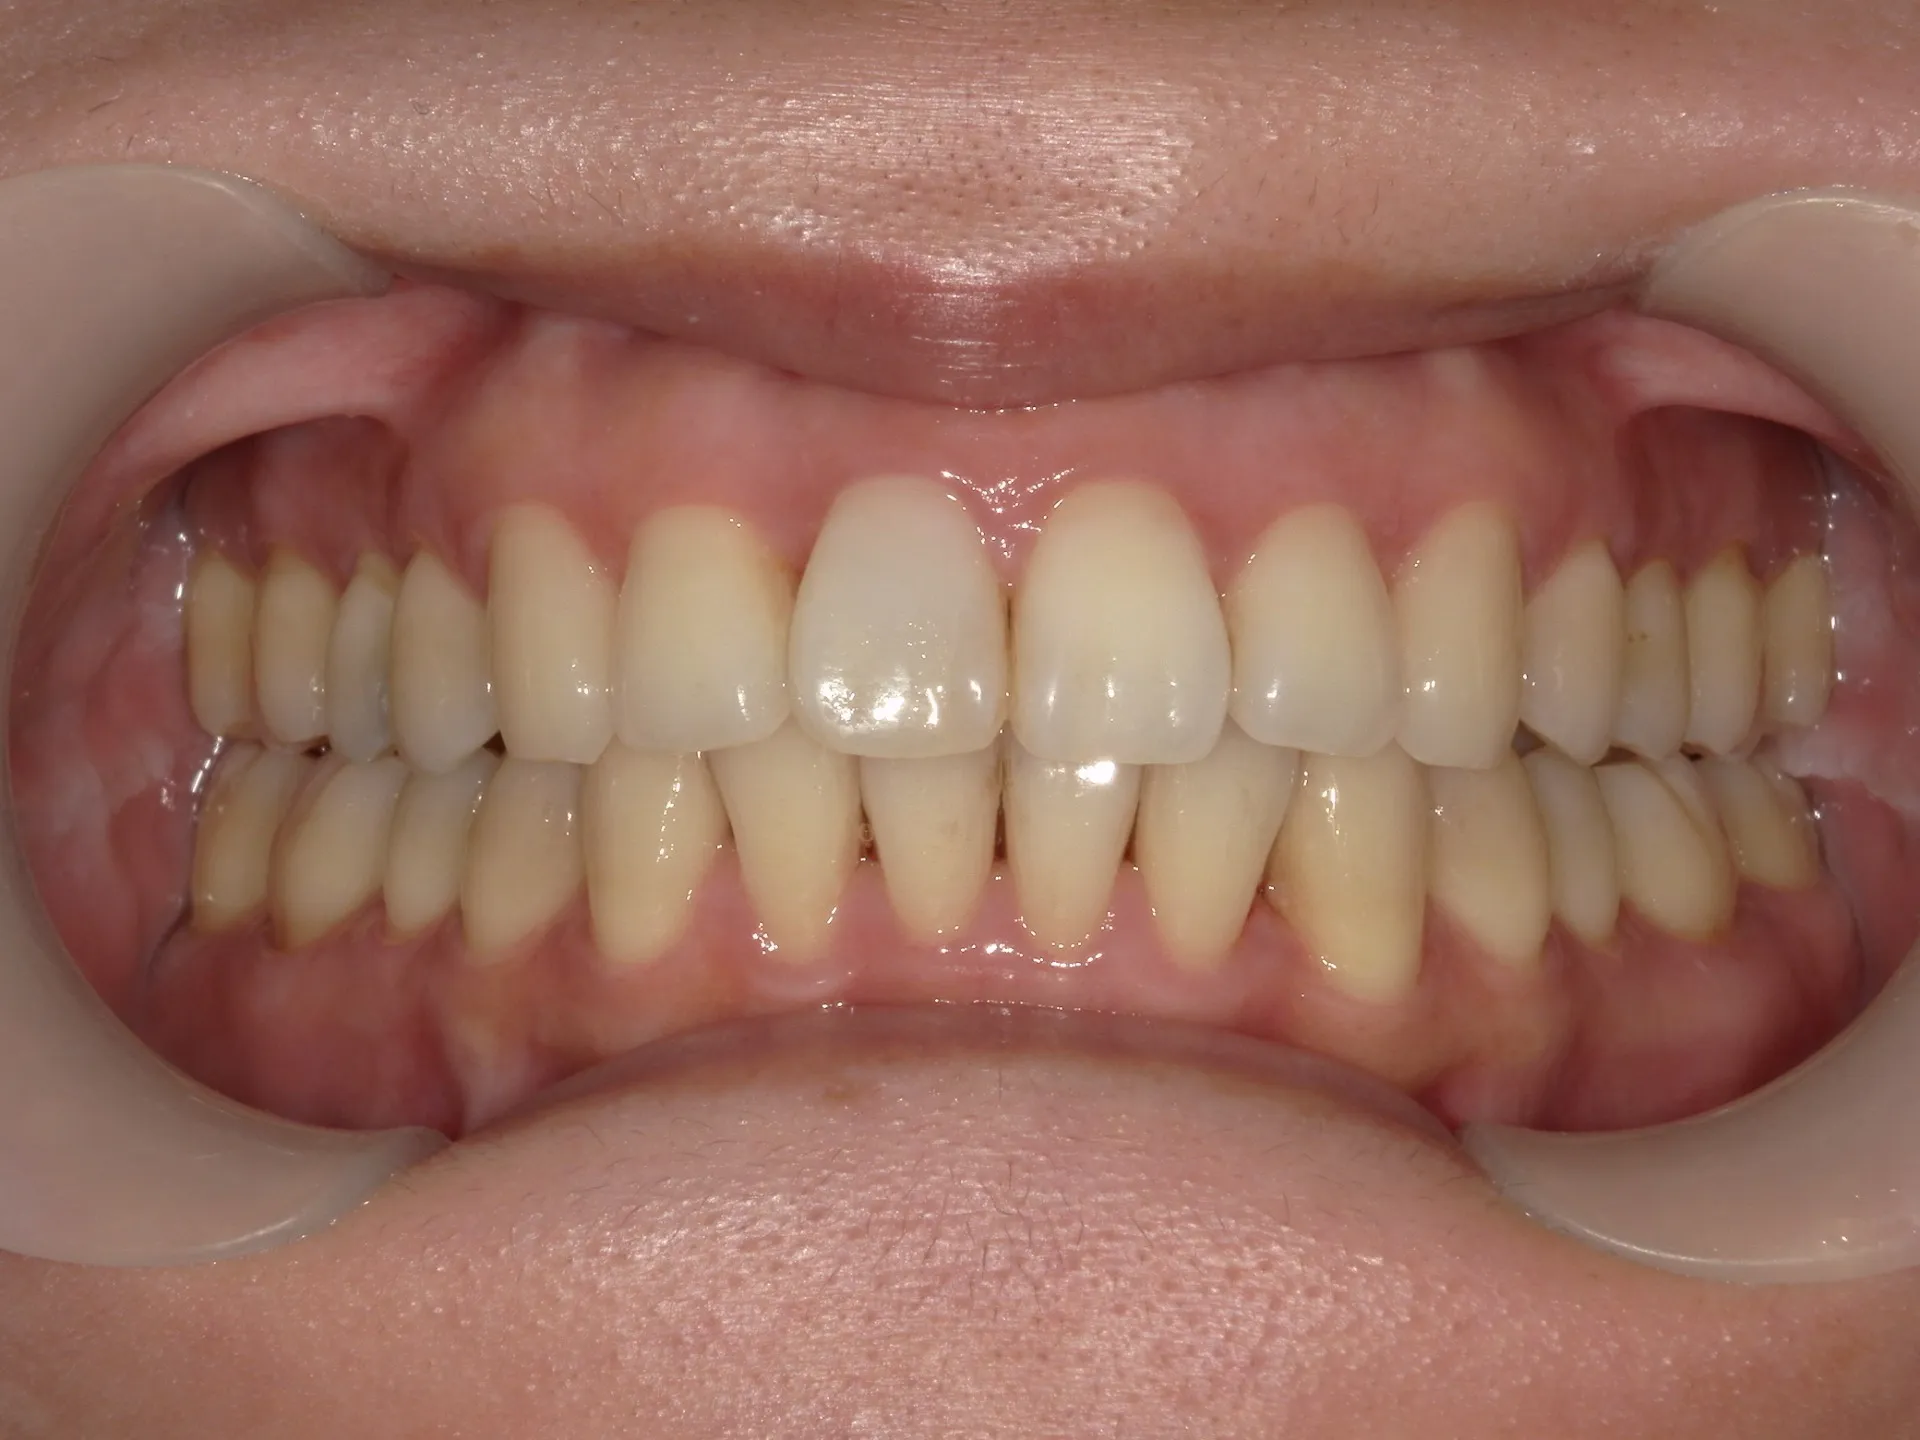

正面観

上の前歯が1本大きくねじれ、更にその歯に変色も見られました。

下の歯もスペースがなくガタついている状態の歯並びでした。

そのため今回は通常の矯正治療とその後にご自身の歯を利用してウォーキングブリーチを行いました。

セラミックの被せ一本で治せた方が、費用感や治療期間は少なくできますが、仕上がりを考えるとやはり今回のようなケースでは、矯正治療とホワイトニングを併用した方が良い選択であったと考えられます。